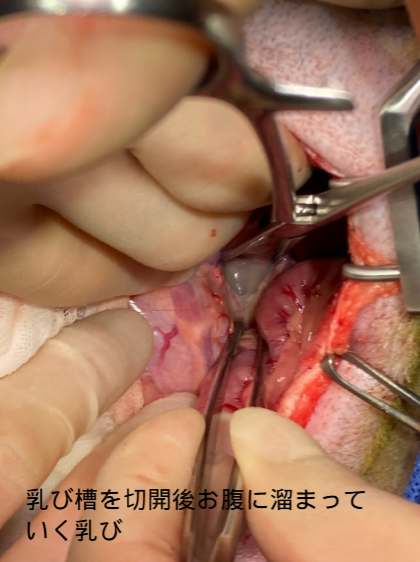

2,乳び槽切開:お腹の中にある乳び槽を切開して、乳びが胸に入らないようにします。

この処置によりお腹に乳びが溜まっていきますが、お腹の中は乳びを吸収する臓器が豊富にあるので問題になることはありません。